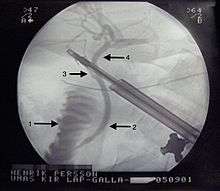

X-Ray during Laparoscopic Cholecystectomy. 1 - Duodenum. 2 - Common bile duct. 3 - Cystic duct. 4 - Hepatic duct. | |